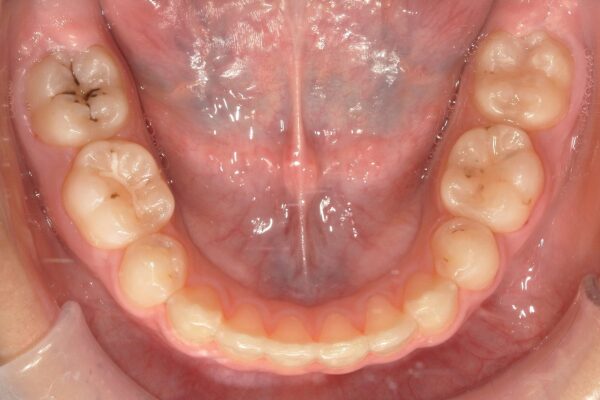

▼2023年12月